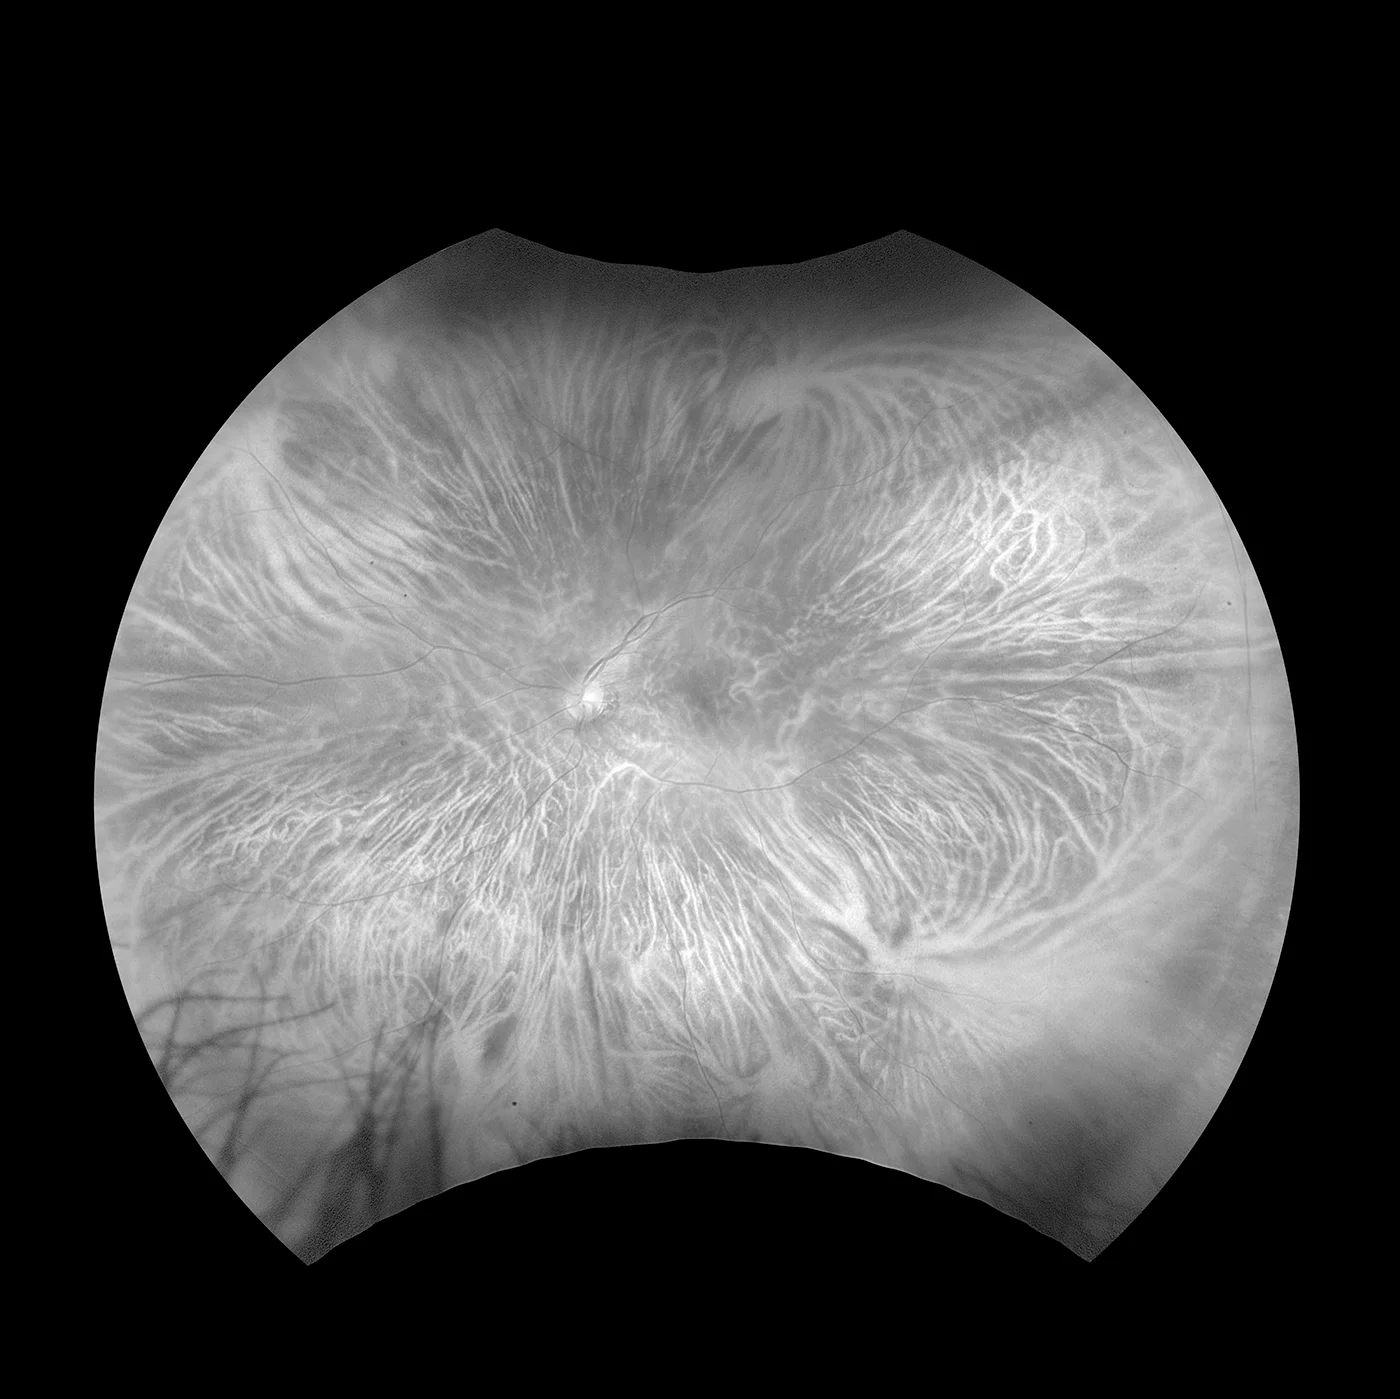

MonacoPro bietet Ihnen faszinierende neue Möglichkeiten, Ihre klinischen Untersuchungen zu vervollkommnen. Als einzige Ultra-Weitwinkel- Bildgebung der Netzhaut mit integriertem SD-OCT liefert Ihnen MonacoPro ein 200° optomap-Bild in weniger als ½ Sekunde und erstellt zudem 40°-OCT-Querschnittsaufnahmen von Netzhautstrukturen. MonacoPro ermöglicht eine schnelle multimodale Bilderfassung mit Farb-, Autofluoreszenz- und OCT-Scans für beide Augen in nur zwei Minuten.

optomap farbe rg und optomap plus (Rot und Grün Laser): |